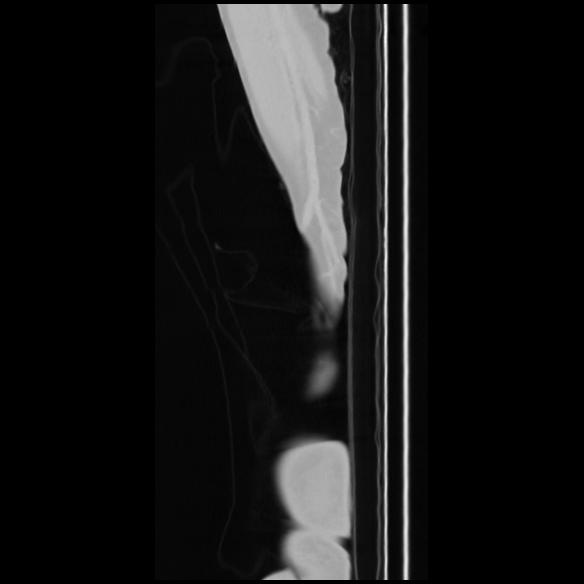

7 CUERPO,CE,Sagittal,3.000,CUERPO,Sagittal,